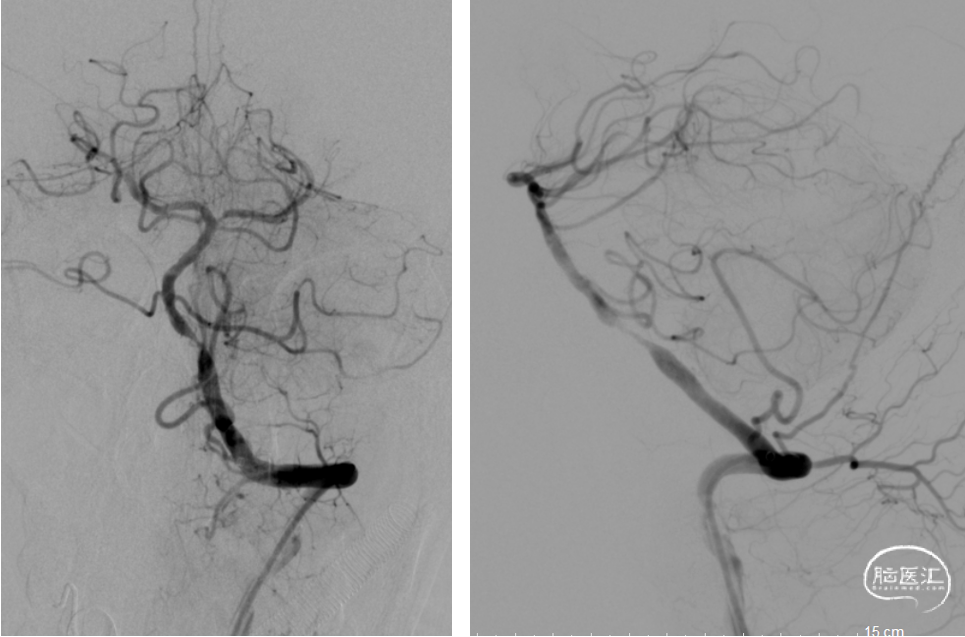

穿刺留置8F动脉鞘,以5F单弯导管行左侧椎动脉造影示:左侧椎动脉PICA以远闭塞。

路图下,在泥鳅导丝导引下将8FGuiding置于左侧椎动脉V2,将Catalyst5 0.058in*132cm沿导引导管置于左侧椎动脉PICA以远闭塞处。

造影示:基底动脉下段可见重度狭窄,远端闭塞,将Catalyst5缓慢通过狭窄处置于闭塞处,负压抽吸可见抽出暗红色血栓,复查造影基底动脉下段重度狭窄,远端显影良好,双侧大脑后动脉、双侧小脑上动脉显影良好,mTICI分级:3级。

DSA:R-V4闭塞

DSA:L-V4闭塞

将Catalyst5置于闭塞处,负压抽吸可见抽出暗红色血栓,复查造影基底动脉下段重度狭窄,双侧大脑后动脉、双侧小脑上动脉显影良好。